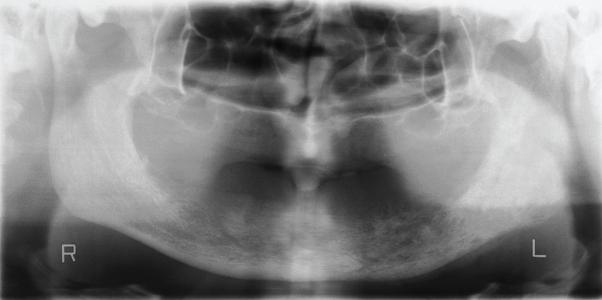

Female breast cancer is one of the major causes of death among women. Metastatic tumors to the maxillo-facial bones are rare. We present diagnosis and treatment of multiple metastatic invasive ductal carcinoma involving massive and early stage the left half of the mandibular body, the floor of the orbit, maxilla, left parietal bone, the iliac bone and cervical and thoracal vertebras in a 36 years old female one and half years after operated.

女性乳腺癌是女性死亡的主要原因之一。发生于颌面骨的转移性肿瘤较为罕见。我们报告了一例36岁女性患者,在接受手术一年半后,出现了多处转移性浸润性导管癌,累及左侧下颌体大部及早期阶段、眶底、上颌骨、左侧顶骨、髂骨以及颈椎和胸椎。